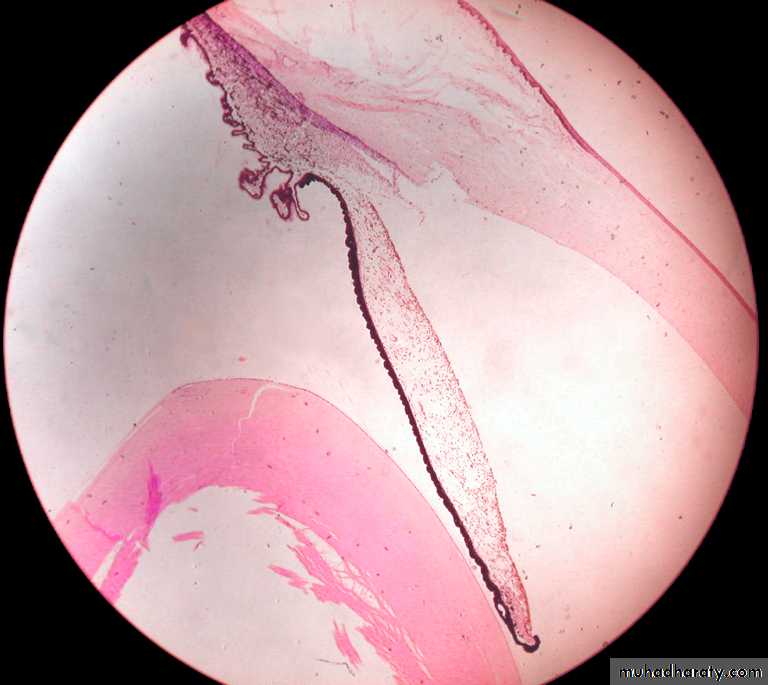

Histology slide of the optic nerve at the optic disc

Optic nerveOptic disc

Vitreous

Optic nerve (blind spot of the retina)

RetinaOptic nerve

Pigment epith

Sclera

Optic disc

Human eye showing: OD optic disc,ON optic nerve, LC lamina cribrosa or cribriform plate, Arrows() are openings in the sclera for the ganglion cells to form the optic nerve, BV blood vessels .